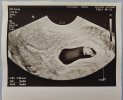

Już jestem po wizycie. Dziecko potroiło wzrost w przeciągu tygodnia, więc zostaje pierwotny termin z OM, czyli 25.03. Lekarz mówi, że brzuch mam już najprawdopodobniej przez wzdęcia na tym etapie ciąży. Ale ogólnie wszystko prawidłowe. Za 2 tygodnie następna wizyta.

Ja też dziś miałam wizyte, wreszcie mam kartę ciąży i doznałam olśnienia że prenatalne z testem pappa są teraz refundowane, w pierwszej ciąży płaciłam za nie prywatnie. Mam 1,3cm fasolki i wiek ciąży dzisiaj wyszedł identyczny jak z OM, termin na 27.03.